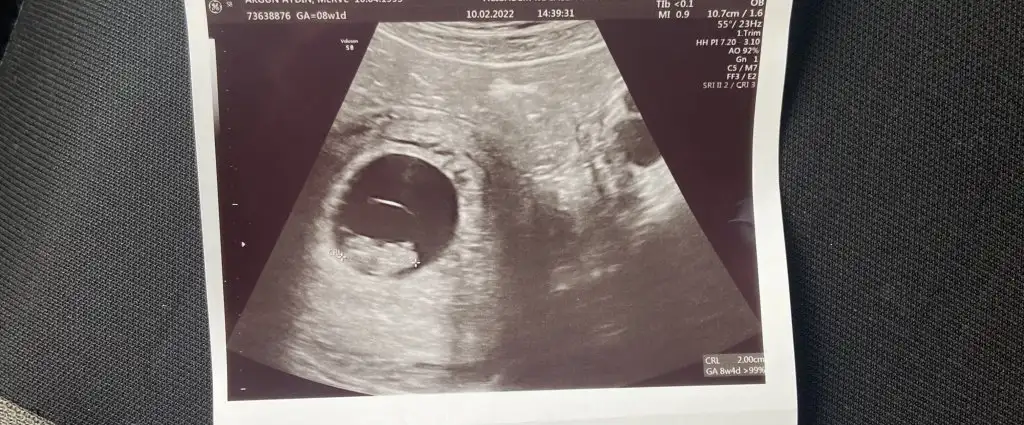

[/B]Eki Görüntüle 473828 gordugunuz gibi ust taraftaki simgedende anlasildigi gibi eger cikinti paralel ise kiz

yok 30°lik bir aciyla yukari dogru bakiyorsa %99 oglunuz olacak demektir simdi bi kac ornek resimler daha koyacagim kiziminkide dahil

Eki Görüntüle 473829 bu bir erkek bebek genital nub cikintisi gayet yukarda

Eki Görüntüle 473831 simdi burada cikintilara bakin eger bel popo cizgisine paralel ise kiz

yok 30 derecelik bir aciyla yukari bakiyorsa erkek

yabancilarin hepsi biliyor bunu biz neden eksik kalalim gayet bilimsel simdi ellerinde11 12 13 ultrason fotografi olanlar alsin hemen baksin yada koyalim buraya yorumlayalim